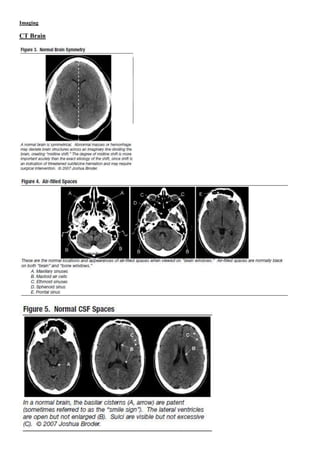

Imaging

CT Brain

Imaging : comment on CXR, CT brain…etc